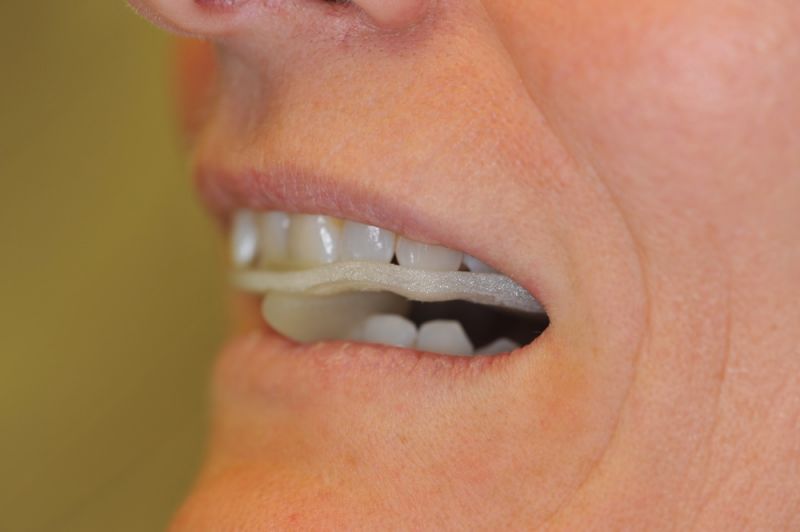

Es läuft dfas Nachweisverfahren einer CMD unter Einsatz eines adjustierten Aufbissbehelfs.

Deutlich erkennbar die Nonokklusion in neuromuskulär zenmtrierter Bisslage